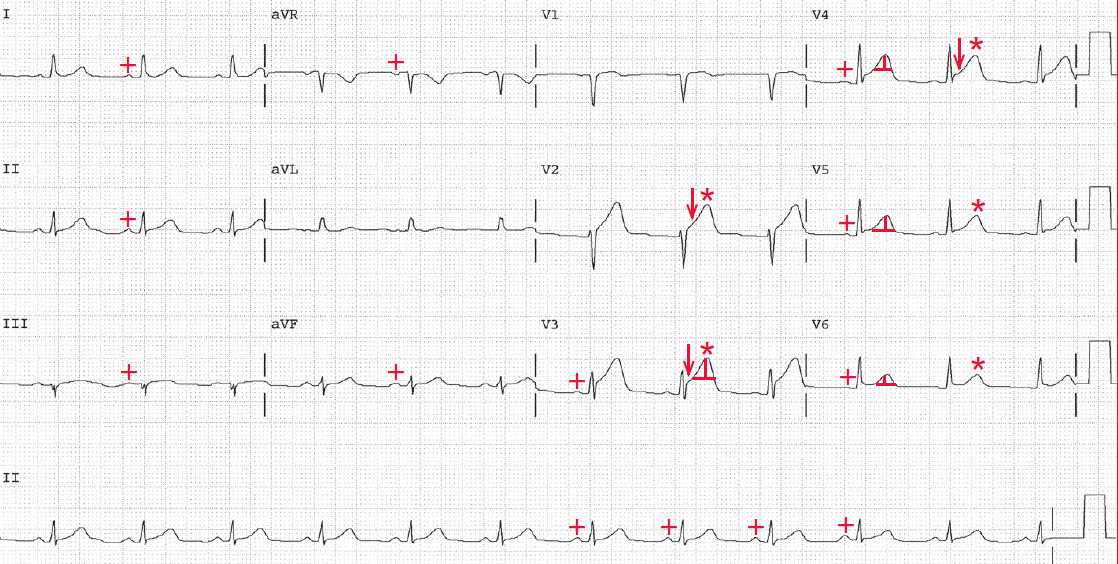

There is a regular rhythm at a rate of 70 bpm. There is a P wave (+) before each QRS complex with a constant PR interval (0.18 sec). The P wave is positive in leads I, II, aVF, and V4-V6. Hence this is a sinus rhythm.

The QRS complex duration is normal (0.08 sec) and the axis is normal, between 0° and +90° (positive QRS complex in leads I and aVF). The QT/QTc intervals are normal (400/430 msec).

There is ST-segment elevation (↓) in leads V2-V4, and the T waves are big and symmetric (*) (hyperacute T waves). This is thus an acute anterior wall myocardial infarction.